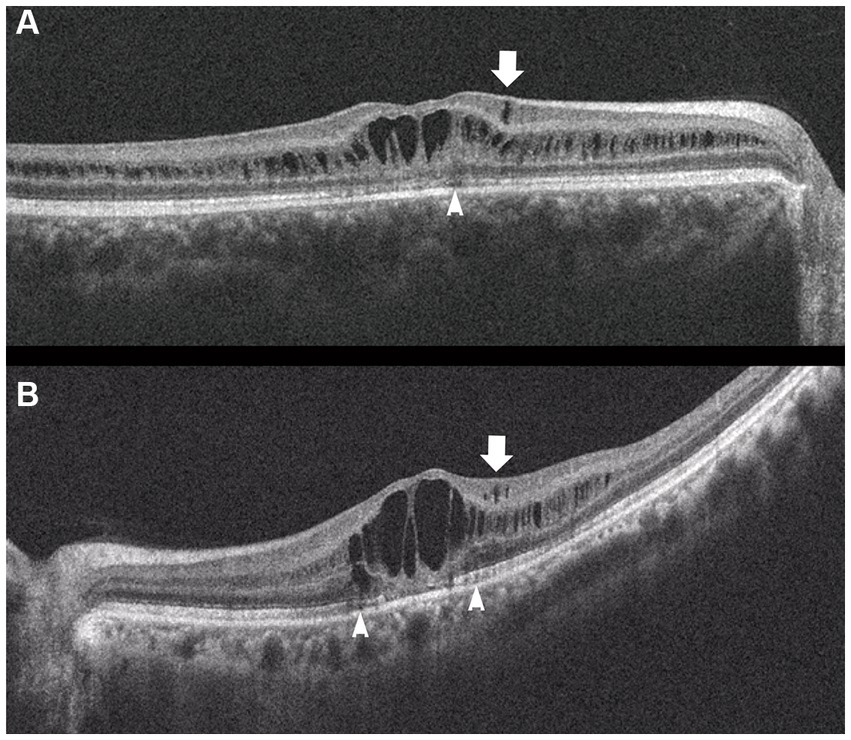

Fundus photograph (A), horizontal images of OCT at line B (B) and line D (D), and magnified image of temporal section of OCT image B (C). Bullous retinoschisis is shown in the inferior retina (A), and OCT image at line B shows splitting of the ganglion cell layer (B,C, Grade 3 in Table 2). OPL, outer plexiform layer; ONL, outer nuclear layer; GCL, ganglion cell layer; RNFL, retinal nerve fiber layer.

In the periphery, OCT revealed that bullous retinoschisis was a result of splitting in the GCL, although many cystoid changes or intraretinal schisis were observed in the INL at the posterior edge of the retinal splitting (Figures 1C, 2B,C). In Patient 2-1, horizontal scanning superior to the fovea revealed intraretinal cystoid changes in ONL, INL, and GCL, but no changes were observed in the retinal nerve fiber layer (Figure 2D). The cystoid changes in the GCL were frequently observed in the periphery but rarely found in the macula (Figures 2C, 3B,C, and 4).

This study reported detailed ultra wide-field OCT findings in the peripheral retina of patients with XLRS. OCT revealed that split and/or cystoid changes in the INL were common to both the macula and peripheral retina. However, cystoid changes in the GCL were observed in the peripheral retina, but rarely in the macula (Figures 2–4). Peripheral retinoschisis resulted from splitting of the GCL (Figures 1C, 2C).